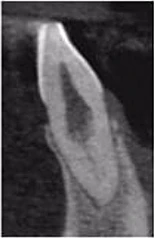

Một phụ nữ 54 tuổi với tiền sử chấn thương tới phòng khám với lý do răng 41 đau và áp xe gây khó khăn khi ăn nhai. Trên XQ 2 chiều thấy tổn thương tiêu ở răng 41 và áp xe ở răng 42 (Hình 1 và 2), rất khó để biết phạm vi nội tiêu theo hướng ngoài – trong. Tổn thương trông có vẻ rộng, nhưng có phá ra phía ngoài hay trong không? May mắn thay, phim chụp từ máy CS 8100 cho thấy nội tiêu chỉ nằm trong phạm vi ống tủy (hình 3 – 5), do đó tôi tự tin rằng điều trị tủy có thể giải quyết vấn đề của bệnh nhân, hai răng này sau đó được đặt Ca(OH)2 rồi trám bít (hình 6 và 7)

Hình 3: Lát cắt ngang trên CBCT

Hình 4: Lát cắt đứng dọc trên CBCT

Hình 5: Lát cắt đứng ngang trên CBCT